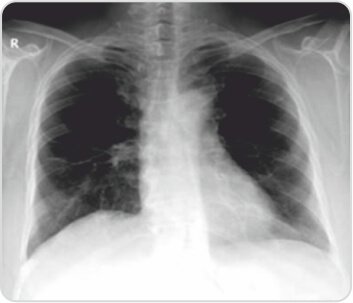

Follow up Chest X ray revealed fibrosis in the right mid zone with the rest of the lung parenchyma appearing normal. Anti PR3 antibodies were 0.24 and her clinical course seemed to have stabilised. BVAS WG score reduced to 1.

Post treatment chest radiograph showingcomplete resolution of right lower lobe consolidation with few fibrotic strands seen at the site of involvement in the right mid zone